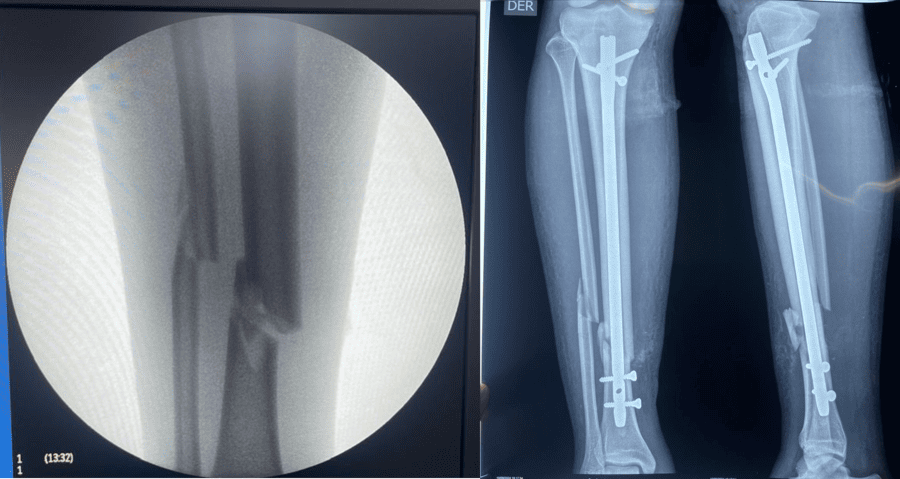

Fracturas de Extremidades

Las lesiones del aparato locomotor suelen ser consecuencia de un traumatismo mecánico, aunque con menor frecuencia se deben a enfermedades óseas (conocidas como fracturas patológicas).

Una fractura es la rotura de un hueso. La mayoría de las fracturas ocurren por una aplicación única de fuerza significativa sobre un hueso normal.

Las fracturas siempre conllevan un sangrado hacia los tejidos adyacentes, cuya magnitud varía según la zona y puede producir hipovolemia o incluso shock. La hemorragia es mayor en fracturas abiertas, que presentan una herida concomitante en la piel (el hueso fracturado no siempre es visible en la herida). Otras complicaciones incluyen daño arterial con isquemia distal de la extremidad o sección nerviosa.

- Agudas (asociadas a lesiones): Sangrado, lesiones vasculares, lesiones nerviosas, síndrome compartimental e infección (osteomielitis).

- A largo plazo: Falta de unión o retraso de la consolidación (el hueso no cicatriza correctamente o tarda más de lo normal), unión anómala (cicatrización en una posición incorrecta), osteonecrosis (muerte del tejido óseo), artrosis (desgaste articular), discrepancia en la longitud del miembro, inestabilidad articular, rigidez y amplitud disminuida del movimiento. La rigidez es más probable si una articulación requiere inmovilización prolongada, siendo rodillas, codos y hombros particularmente propensos, especialmente en ancianos.